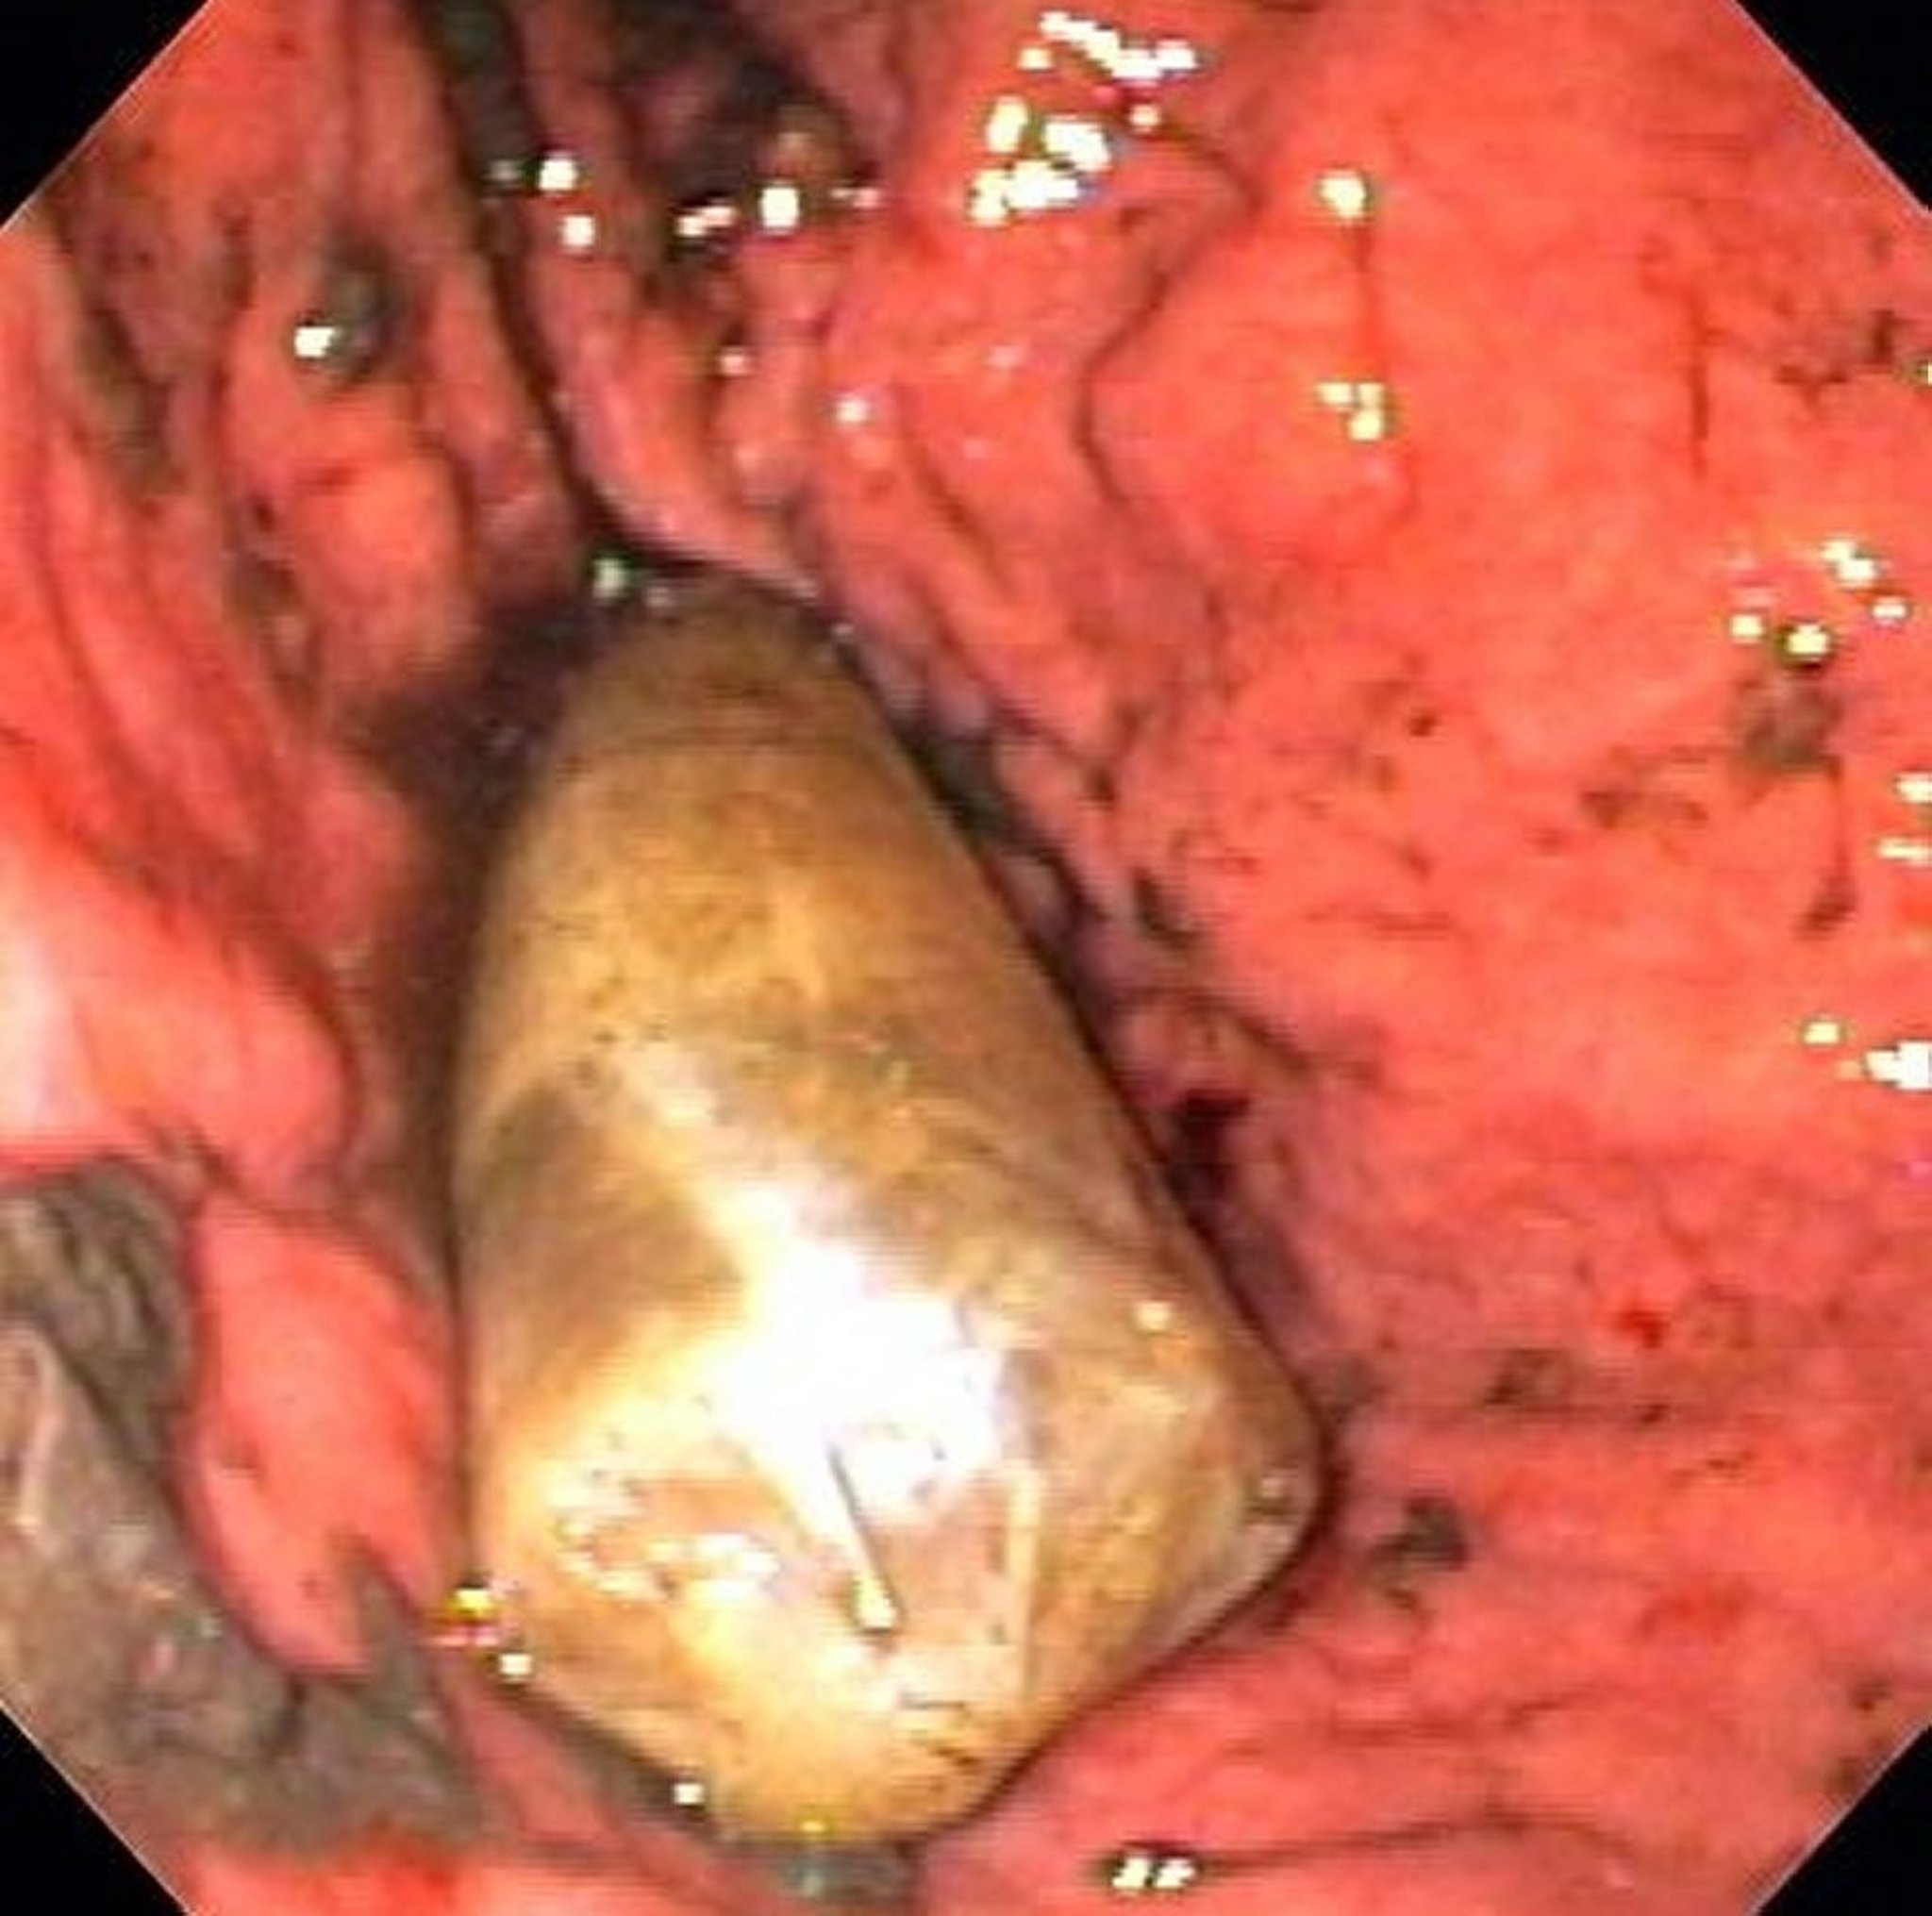

Corpo estraneo nello stomaco (endoscopia)

L’immagine mostra un pacchetto contenente droga inserito nello stomaco.

Immagine fornita da Alan Gingold, D.O.